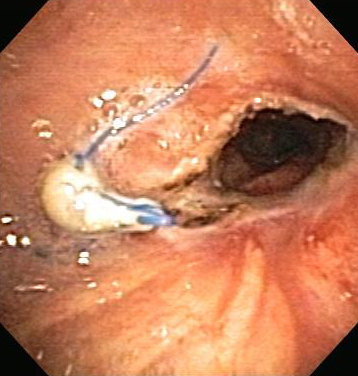

In general, endoscopic management involves less risk, discomfort, and morbidity than surgical treatment.[Figure caption and citation for the preceding image starts]: Post-lung transplant anastomotic bronchial stenosisFrom the collections of Jose Fernando Santacruz MD, FCCP, DAABIP and Erik Folch MD, MSc; used with permission [Citation ends].

[Figure caption and citation for the preceding image starts]: Post-lung transplant anastomotic bronchial stenosis: right mainstem anastomosis post-multimodal endoscopic therapyFrom the collections of Jose Fernando Santacruz MD, FCCP, DAABIP and Erik Folch MD, MSc; used with permission [Citation ends].